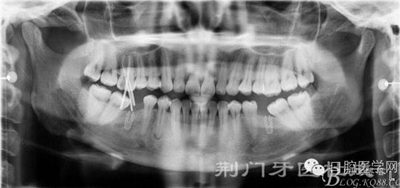

X線片